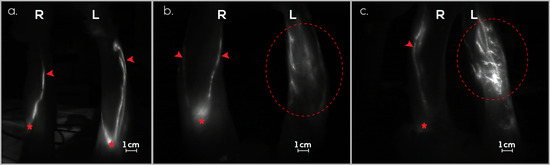

3.1. Treatment Group (G1)

3.2. Preventive Group (G2)

3.3. Control Group (G3)

3.4. Follow-Up Assessments